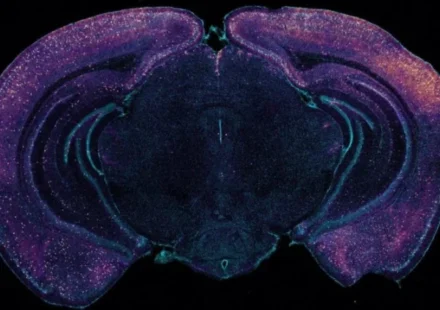

Новое научное исследование опровергает устоявшееся представление о тотальном возрастном угасании мозга. Оказывается, некоторые его отделы не только не деградируют с годами, но и становятся сильнее. К такому выводу пришла группа нейробиологов из Германии,…

Ученые, воздействуя лазерами на клетки мозга, определили источник иллюзий, открыв новые данные о природе шизофрении. Новое исследование о том, как мозг обрабатывает иллюзии, заключалось в облучении нейронов мышей лазерами, что позволило искусственно…